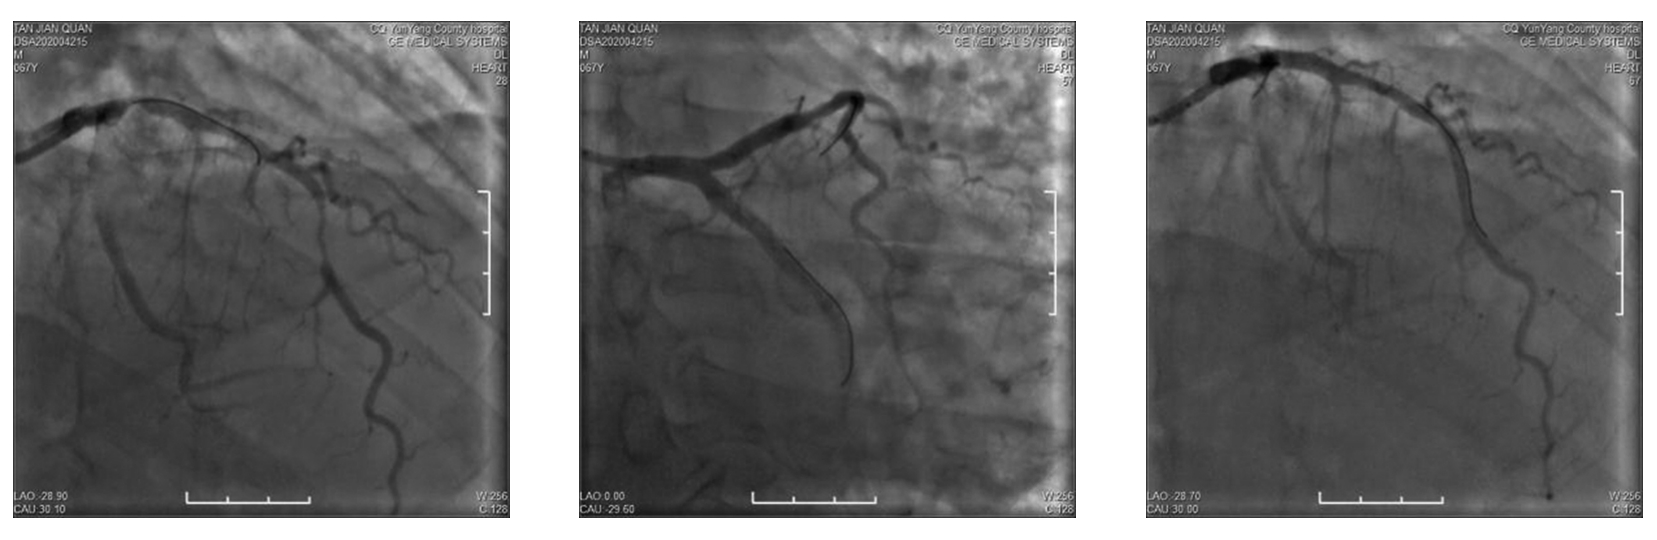

• 疑似雷帕霉素药物洗脱支架术后Kounis综合征1例

2024, 49(1):97-100. DOI: 10.13406/j.cnki.cyxb.003409

摘要 (42) HTML (15) PDF 1.14 M (104) 评论 (0) 收藏

摘要: